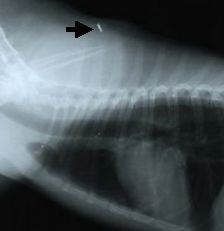

ISO規格のマイクロチップをISO規格用の「読み取り器」で読めばわかりますが、非ISO規格のものはISO規格専用の「読み取り器」では読めません。例えばマイクロチップをしてあるペンダンドのようなサインがあるのに「読み取り器」でよめない場合や、規格が違うため「読み取り器」で読めない場合に、マイクロチップ(MC)の有無を確認するには、マイクロチップ(MC)のありそうな場所を触診(手でさわりその感触で確かめる)で確かめることも猫の場合などは、可能な場合もありますが、最も確実なマイクロチップの存在する部位を調べるには、X線検査(レントゲン撮影)によってその有無を調べる方法です。

![]() |

マイクロチップを装着した犬のX線写真